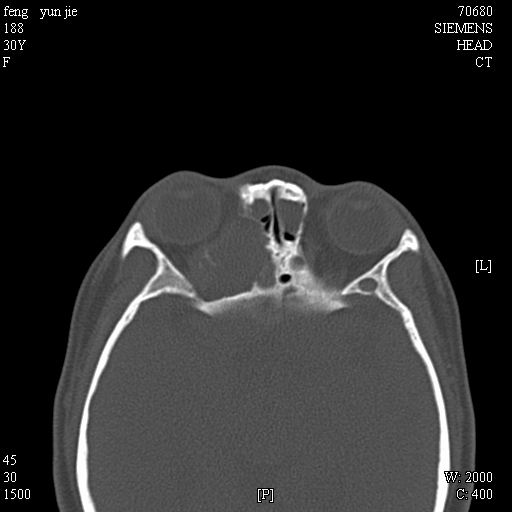

女,37岁,多年前鼻骨骨折过,现在穿刺有炎性分泌物

考虑:1、鼻骨陈旧性骨折;

2、额窦粘液囊肿(右侧水平额窦突入眶内上方)可能性大。

1)左侧鼻骨骨折(陈旧性)。2)双侧额窦及双侧筛窦炎症,伴右侧额筛窦黏液囊肿突入右侧眼眶。